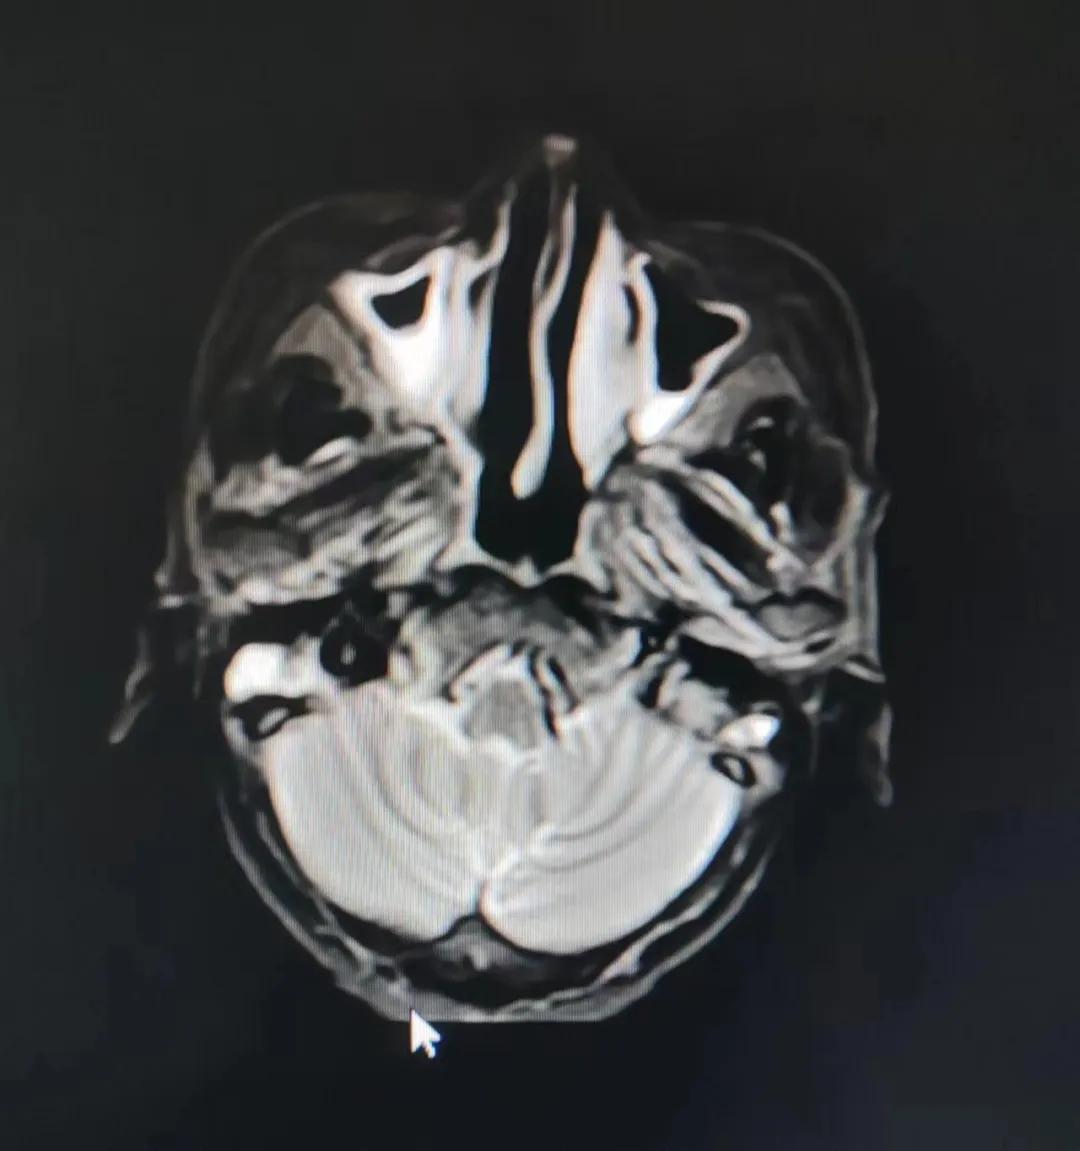

70歲的彭阿姨,5個月前因鼻部瘙癢伴流血不止在當(dāng)?shù)卦\所治療,瘙癢和出血癥狀不但沒有得到有效控制,反而進(jìn)行性加重,并出現(xiàn)鼻腔堵塞、進(jìn)食困難,經(jīng)外院病理活檢確診為“鼻腔惡性淋巴瘤”。不斷加重的病痛已嚴(yán)重影響了老人的生活質(zhì)量,為求診治,患者及家屬于今年2月份慕名來到了市二院放療科。

治療前

老人因鼻部腫物堵塞鼻腔并且侵犯鼻咽導(dǎo)致鼻塞、疼痛、吞咽困難,身心都備受煎熬,趙亮主任在詢問其病史期間幾度落淚。趙亮主任向患者及家屬解釋說:“現(xiàn)代放療比過去的傳統(tǒng)放療設(shè)備先進(jìn),技術(shù)不斷提升,能對腫瘤區(qū)域的照射劑量進(jìn)行優(yōu)化,做到準(zhǔn)確定位、精準(zhǔn)照射,同時,最大限度地降低正常組織的受量,對全身情況影響很小。”

考慮到患者年齡較大、體質(zhì)差,手術(shù)難度大,且常規(guī)的放射治療難以保護(hù)患者晶體造成患者雙眼視力損傷,放療團(tuán)隊以最快的速度制定了精準(zhǔn)放射治療方案并開始為其實施治療。僅僅數(shù)日后,老人腫塊出血即得到控制,腫塊明顯縮小,放療20次后腫塊迅速縮??!

治療后

放療結(jié)束,除了放療處的皮膚輕微放射性皮炎外,基本沒有什么不良反應(yīng)。復(fù)查發(fā)現(xiàn),鼻腔淋巴瘤已不可見,目前患者已康復(fù)出院。